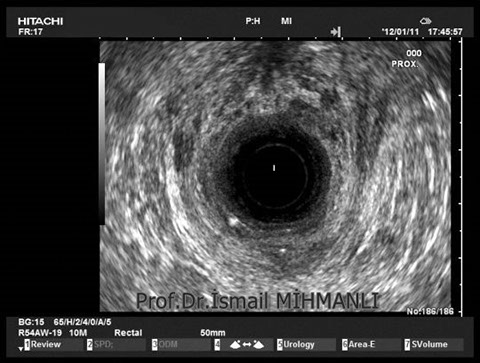

PERİANAL FİSTÜLLER Perianal fistül ve abselerin intersfinkterik anal bez iltihabından kaynaklandığı düşünülmektedir. Crohn hastalarında perianal enflamatuvar hastalık sıktır. İntersfinkterik mesafedeki enfeksiyon yukarıda rektuma, aşağıda cilde, yanlarda dış sfinkteri geçerek iskiyoanal mesafeye uzanabilir. Primer fistülün sfinkterler ile ilişkisini ve abse veya sekonder dal varlığını ameliyat öncesi bilmek, tedavi planı açısından önemlidir. İskiyoanal ve iskiyorektal mesafe tutulmamışsa hastalık daha kolay tedavi edilir. Bu mesafelerde abse veya sekonder bir dal varsa fistül komplekstir ve tedavisi kompleks olmayan fistüle göre değişik olabilir. Bundan dolayı, primer fistül traktı anatomik yerleşimine göre geleneksel olarak sınıflandırılır. Bu sınıflama dörde ayrılır: 1- İntersfinkterik (iç ve dış sfinkter arasında), 2- Transsfinkterik (dış sfinkteri geçerek iskiyoanal veya iskiyorektal mesafeye ulaşmış), 3- Suprasfinkterik (intersfinkterik plandan yukarı doğru uzanan traktüs puborektal kasın Genel Gaz ve Dışkı Kaçırma (Anal İnkontinans) Perianal Fistüller Rektal Tümörler Anal Tümörler Kabızlık Yazılarımız üstündeki bir seviyeden yana kıvrılarak tekrar aşağıya iskiyoanal mesafeye uzanmış), 4- Ekstrasfinkterik (sfinkterlerin dış tarafında rektumdan direkt olarak perianal cilde uzanan traktüs). Endoanal ultrason ile hem primer fistül, hem de varsa sekonder dal ve abse doğru bir şekilde tanınır. Endoanal ultrason ile fistülün anal kanala açılan kısmını (iç uç) görmek kolaydır. Bu hastalarda sfinkter defektlerine de rastlanmaktadır. Sfinkter defekti endoanal ultrason ile kolaylıkla tespit edilir. (bkz. anal inkontinans) Perianal fistül şikayeti olan hastaların az kısmında endoanal ultrason ile bir şey görülemez ise endoanal ultrason probuna ek olarak lineer prob ile anal kanal çevresine bakmak yararlıdır. Çünkü anal kanal bileşenlerinin uzağındaki bir enflamasyon ancak bu problar ile tanınabilir.

Crohn hastasında parİanal enflamatuvar hastalık